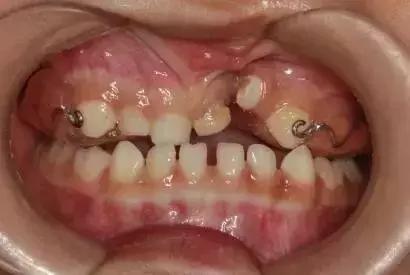

03

上颌颌垫活动矫治器

简单点说,就是喊你把这个上颌颌垫活动矫治器戴到起。

04

下颌斜面导板矫治器

还是简单点说,喊你把这个下颌斜面导板矫治器戴到起。你是不是要问“那跟上面那个有啥不同嘛”?回答:因为娃娃的患病情况不同嘛!